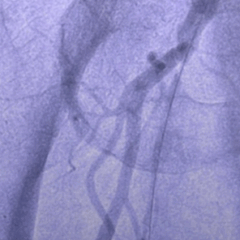

Jetstream : Innovation en Recanalisation Fémorale